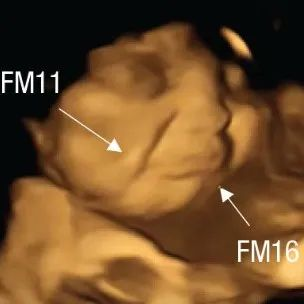

[研究进展] 胎儿在子宫内能竟对味觉和嗅觉有喜好反应?胎儿通过羊水可以品尝和闻味_生 日期:2022-10-11 17:17:16 点击:110 好评:0

近日,科学家对100名孕妇进行了4D超声波扫描,用以了解未出生的婴儿对母亲所吃食物的味道的反应如何。...